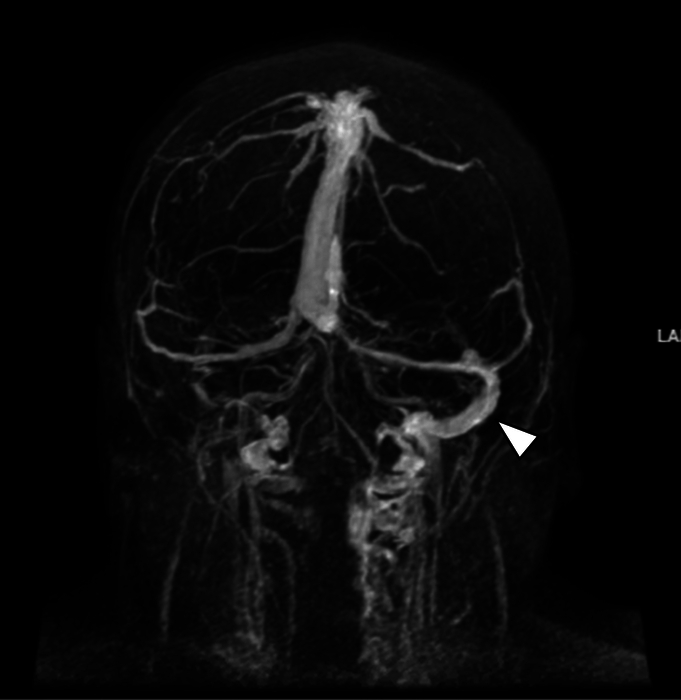

Case report: This case report describes a young woman with CVST who did not respond to low-molecular-weight heparin (LMWH). The patient was initially treated with LMWH; however, her symptoms and clot burden in the sagittal sinus worsened, and coagulation studies showed no evidence of therapeutic anticoagulation despite good compliance. Unfractionated heparin was then initiated, and the patient's symptoms improved dramatically within 24 hours, along with the recanalization of the cerebral venous sinuses. Genetic testing revealed a heterozygous mutation in the prothrombin gene (G20210A). This mutation is a known risk factor for CVST. However, it is unclear why the patient did not respond to LMWH but responded appropriately to unfractionated heparin.

Abstract Image